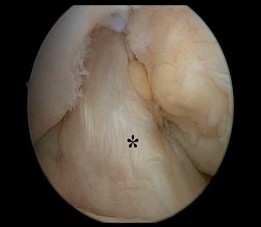

Figure 12 shows an arthroscopic view from an inferolateral portal of a right knee. The asterisk indicates which structure?

The asterisk indicates the anteromedial bundle of the anterior cruciate ligament. The anterior cruciate ligament consists of 2 functional bundles: anteromedial and posterolateral. During extension of the knee, the posterolateral bundle becomes taut. In flexion, the anteromedial bundle is tight and the posterolateral bundle relaxes. Recently, techniques for double-bundle reconstruction have been described to recreate the normal anatomic relationship of the 2 bundles.